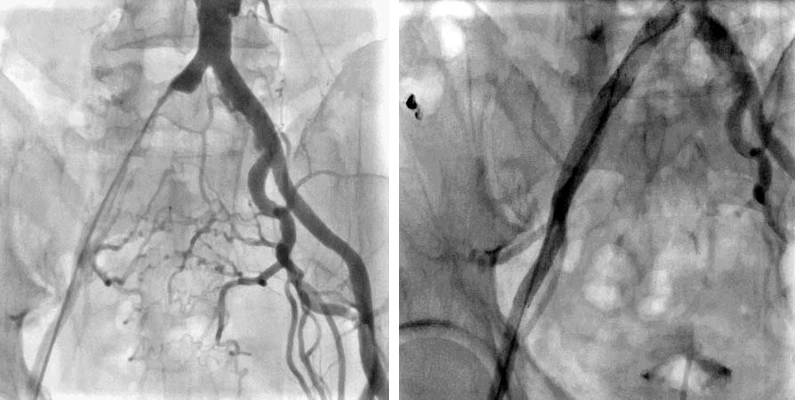

- 大動脈狭窄 【写真】

- 高位大動脈閉塞(Leriche synd) 【写真】

- 腸骨動脈完全閉塞(右) 【写真】

- 腸骨動脈狭窄 【写真】

- 浅大腿動脈狭窄 【写真】

- 浅大腿動脈閉塞 【写真】

- 3枝閉塞 【写真】

- 脛骨腓骨動脈幹(peroneal trunk) 【写真】

- 後脛骨動脈(posterior tibial artery) 【写真】

- 腎動脈 【写真】

- 鎖骨下動脈 【写真】

考え方としては、早期であるほど2の血管内手術のみで治る可能性が高いと考えてよいでしょう。現在の末梢動脈に対する血管内手術の適応は、大動脈・腸骨動脈領域から膝下動脈、さらに足関節から足趾にまで及びます。しかし、それぞれの治療法には当然ながら適応があります。このためしばしば従来からの手術との組み合わせであるハイブリッド手術が必要になりますが、血管内呪術の関与する割合は8~9割にも及んでいます。